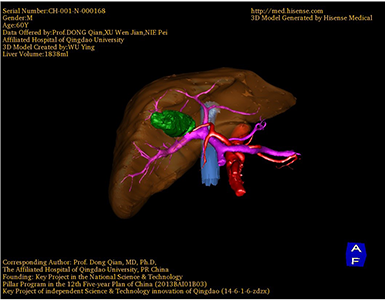

将0.625mm双源薄层CT资料的静脉期和动脉期Dicom格式文件导入海信CAS系统。

通过调节窗宽窗位调整CT序号,对肿瘤,肝实质,胆囊,下腔静脉,肿瘤,肝动脉、门静脉及肝静脉等进行三维重建;系统自动计算肿瘤体积和肝脏体积。

术前手术方案的规划。

麻醉成功后,病人平卧位,常规碘伏消毒手术区皮肤,铺无菌巾、单。取上腹部反“L”型切口,长约20cm,分层入腹,保护切口,置框架拉钩。洗手探查:肝脏质地韧,IVb段可扪及大小约2.5cm肿物,胆囊张力高,与周围粘连,胆囊底部可触及质硬肿块,约3cm*4cm大小,肝门部可触及多枚肿大淋巴结。胆总管无明显扩张。胃肠(-)。决定行胆囊癌根治性切除+肝脏IV、V段部分切除+肝门淋巴结清扫术。分离粘连,显露肝门,仔细解剖,自十二指肠上方清扫脂肪及淋巴组织。解剖肝门部组织,骨骼化胆总管,肝固有动脉,门静脉,断扎胆囊管及胆囊动脉。在肝脏表面Ⅳ、Ⅴ段做预定切线,阻断第一肝门,依次钳夹、切断肝组织,结扎相应的门静脉分钟与肝静脉分支,将部分肝Ⅳ、Ⅴ段及胆囊整块切除。松开阻断,阻断时间16分钟。肝断面渗血处分别缝扎止血,温蒸馏水1000ml冲洗腹腔,止血,创面覆盖止血敷料。于小网膜孔置引流管1根于右侧腹壁穿孔引出。清点纱布器械无误,分层缝合腹壁切口。手术顺利,麻醉平稳,术中出血约50ml,未输血。术后血压/mmHg,心率次/分。术后病人入PACU。标本:剖开胆囊可见肿物位于胆囊底部,大小约4cm×3cm,色灰白,质硬。肝脏IVb段内可见灰白色肿物,约2.5cm×2cm。标本经病人家属过目后送病理检查,结果回示:(胆囊)低分化鳞状细胞癌(大小3.5*3*2.5cm)。手术时手术者可开启Hisense CAS系统手势控制功能,对肿瘤的解剖结构进行实时、全方观察、评估,起到术中导航作用。

术前三维重建:

重建图片